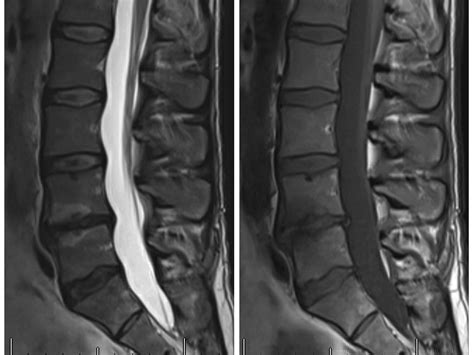

• Pre-Procedure Preparation: Before the procedure, patients undergo a thorough evaluation to determine if they are suitable candidates. This includes medical history, physical examination, and imaging tests such as MRI or CT scans.

• Have been diagnosed with vertebral endplate abnormalities, which are often associated with chronic low back pain.